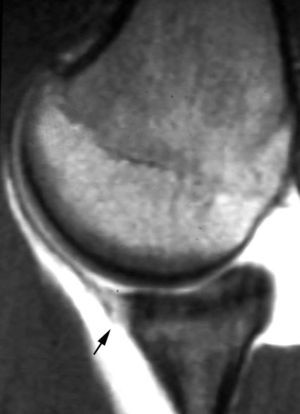

POLPSA (posterior labral periosteal sleeve avulsion)

Esta lesión se asemeja a la ALPSA, pero ocurre en el borde glenoideo posterior. El LG se halla desplazado hacia dentro y por detrás del borde glenoideo posterior. El mecanismo de producción del POLPSA es una dislocación posterior, y por tanto se puede encontrar también un Hill Sachs invertido19 (fig. 14).

. Artrorresonancia axial T1 con supresión grasa donde se observa una rotura del labio glenoideo posterior con desplazamiento posteromedial (flecha). Nótese la situación del labio glenoideo en comparación con una rotura sencilla, no desplazada, que se observa en la figura 13. Obsérvese la presencia de una lesión de Hill-Sachs invertida (cabezas de flecha), en relación con una dislocación posterior con reducción.Lesión de Bennett